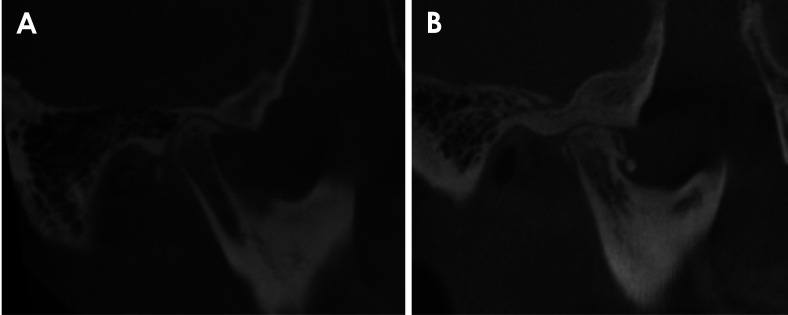

Abstract Image